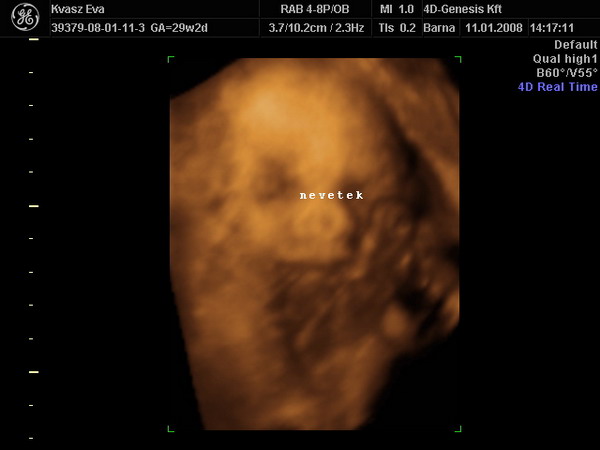

26 hetesen2007.12.13 20:04